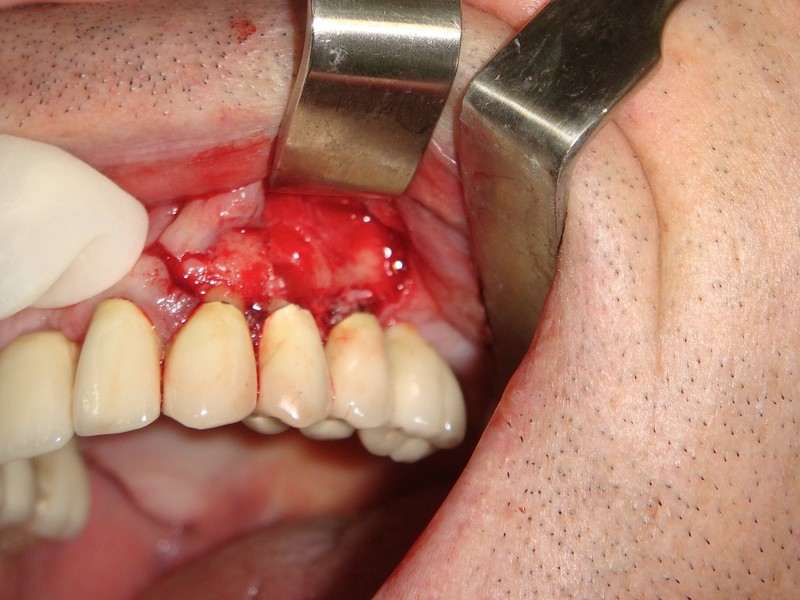

rigenerazione grave difetto parodontale a carico una intera emiarcata